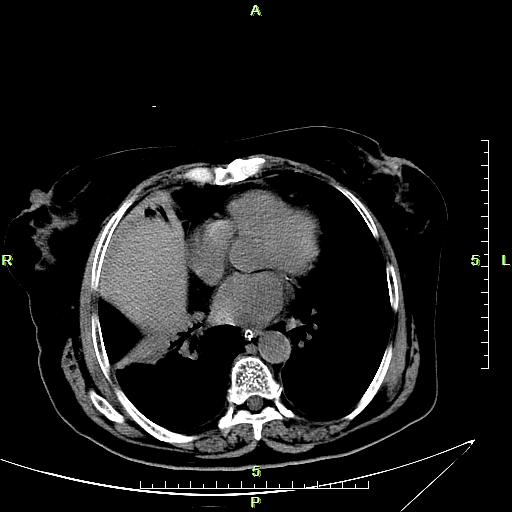

CT51909:上腹部CT,请会诊!

本帖最后由 cefcmj 于 2016-5-5 22:38 编辑 女,70岁,右上腹疼痛5天伴发热。

肝右叶见低密度影,胆囊壁增厚且强化,周围见低密度影,未见强化,右侧胸腔少量积液,考虑:1.肝右叶囊肿。2.急性胆囊炎伴胆囊窝积液。3.右侧胸腔积液。

肝右叶见低密度影,胆囊壁增厚且强化,周围见低密度影,未见强化,右侧胸腔积液。考虑:急性胆囊炎伴胆囊窝积液,肝右叶囊肿,右侧胸腔积液。

急性化脓性胆囊炎伴胆囊窝少量积液。

急性化脓性胆囊炎或胆囊癌,结合临床

胆囊壁不均匀增厚,胆囊窝区肝脏密度减低,强化不均匀,考虑:胆囊癌累及肝脏可能。

1、支持急性胆囊炎并胆囊窝积液;

2、肝右叶小囊肿;

3、右肺下叶肺不张可能,右侧胸腔积液;